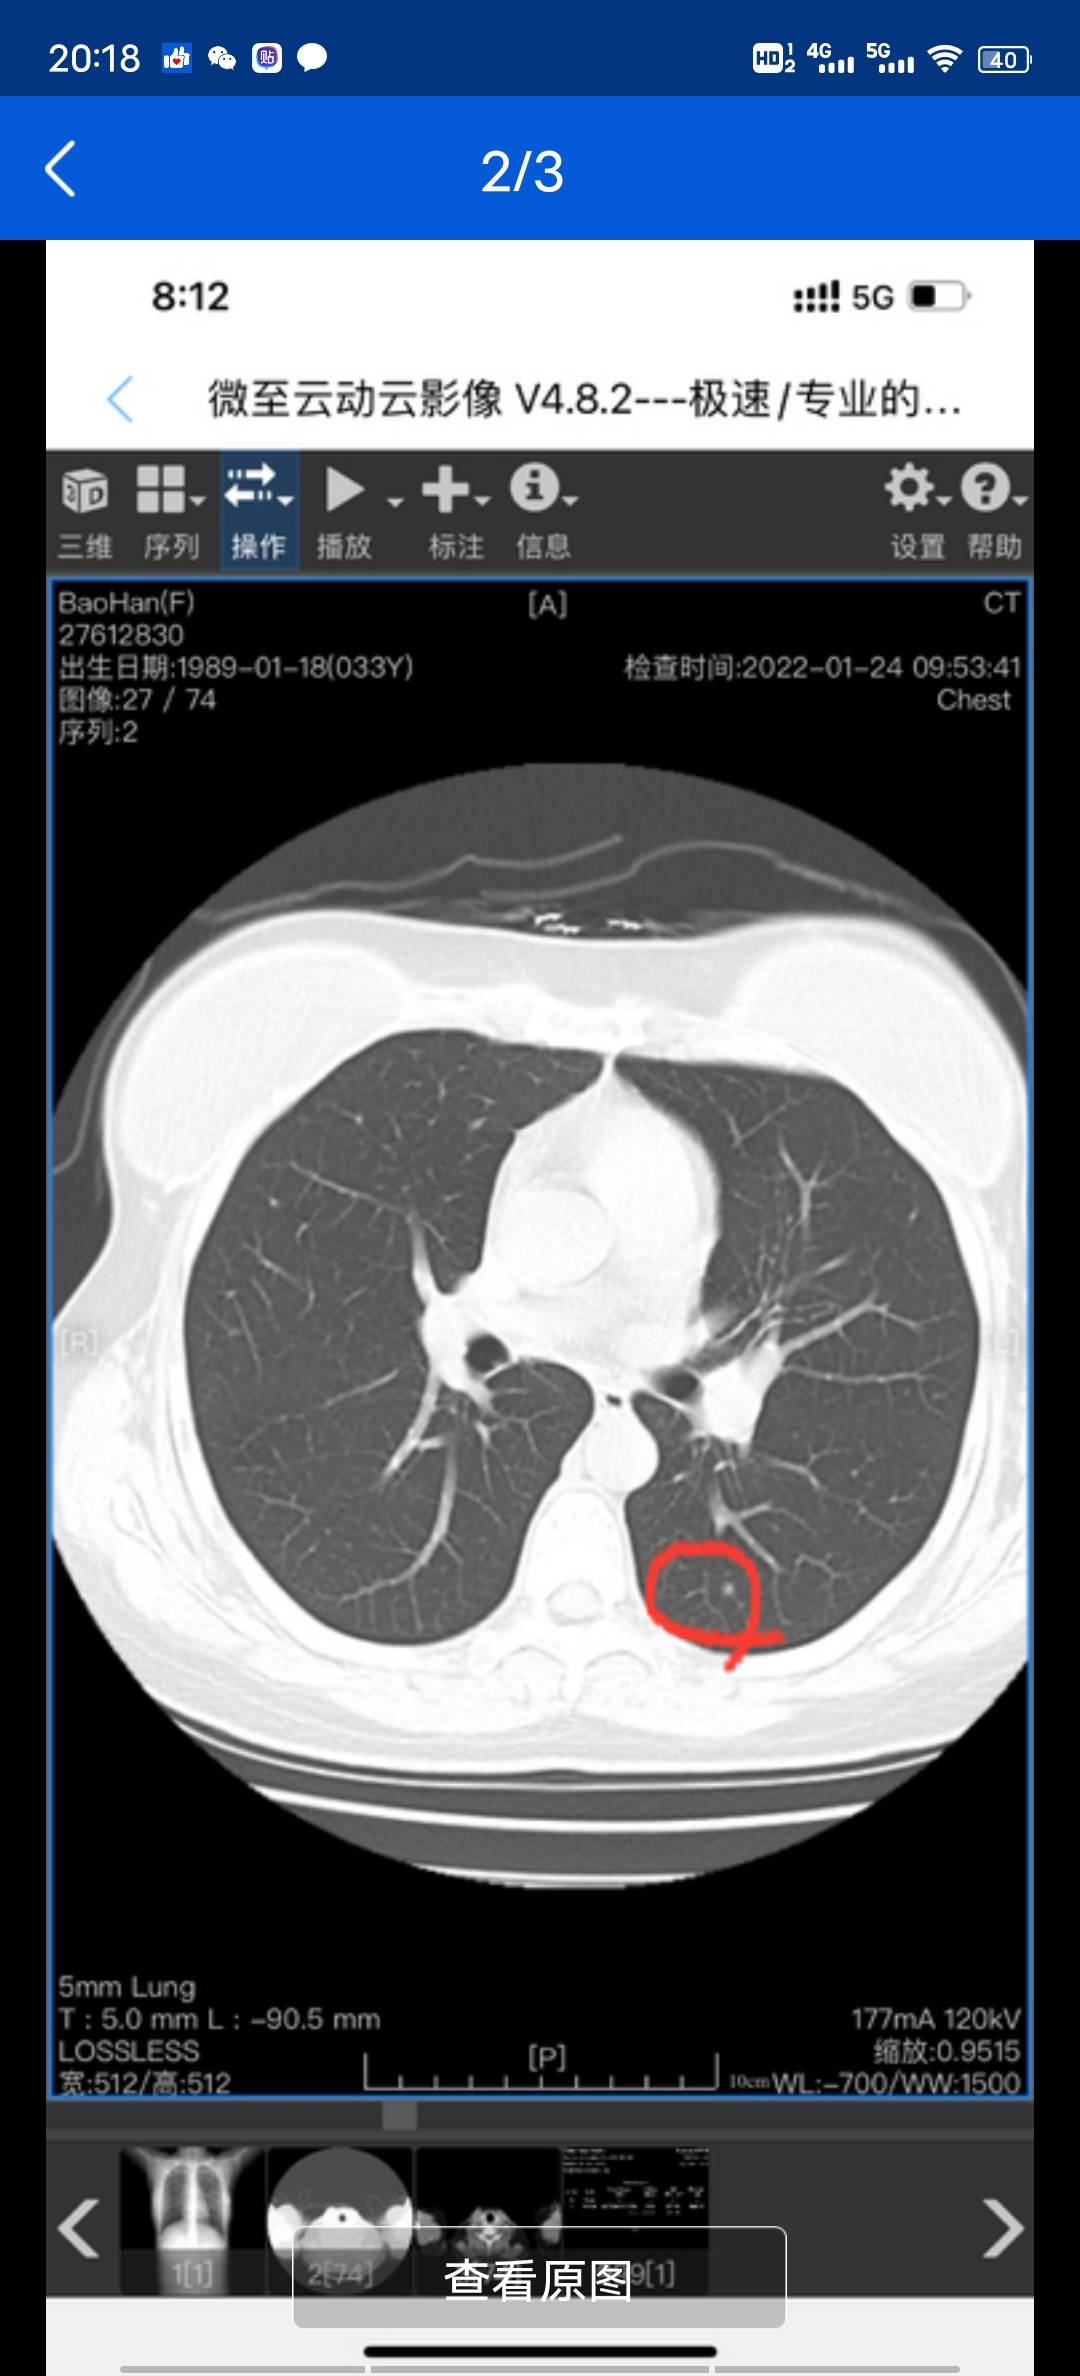

乳腺癌术后一年,新增两个肺结节,会是转移的么图片

我12月复查肺也有3mm结节,医生让随访,准备过完年再去做个cT。你的情况医生怎么说的啊